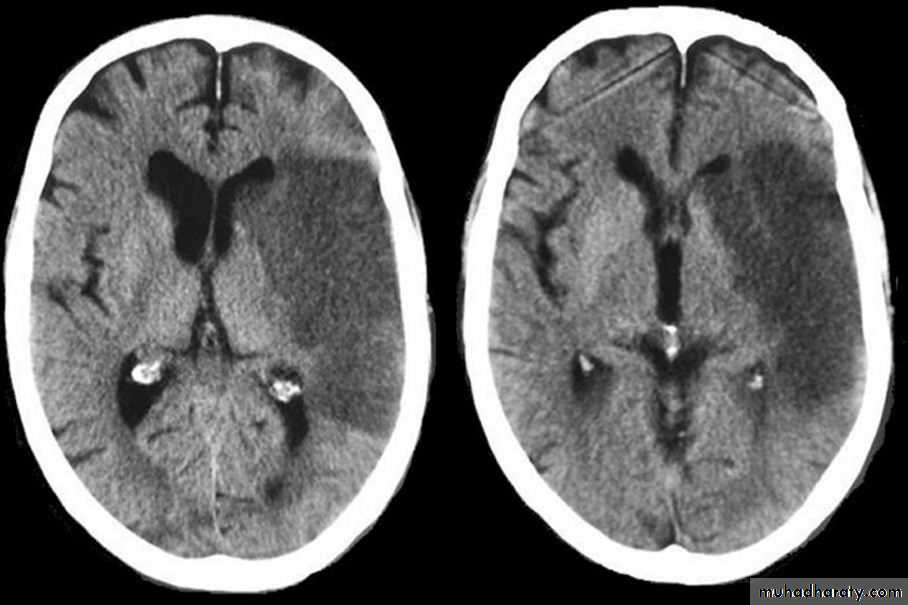

Imaging in Acute Stroke

• Role of CT and MR in patients with stroke• Early CT and MR signs of infarction

• Exclude hemorrhage• Differentiate between irreversibly affected brain tissue and reversibly impaired tissue (dead tissue versus tissue at risk)